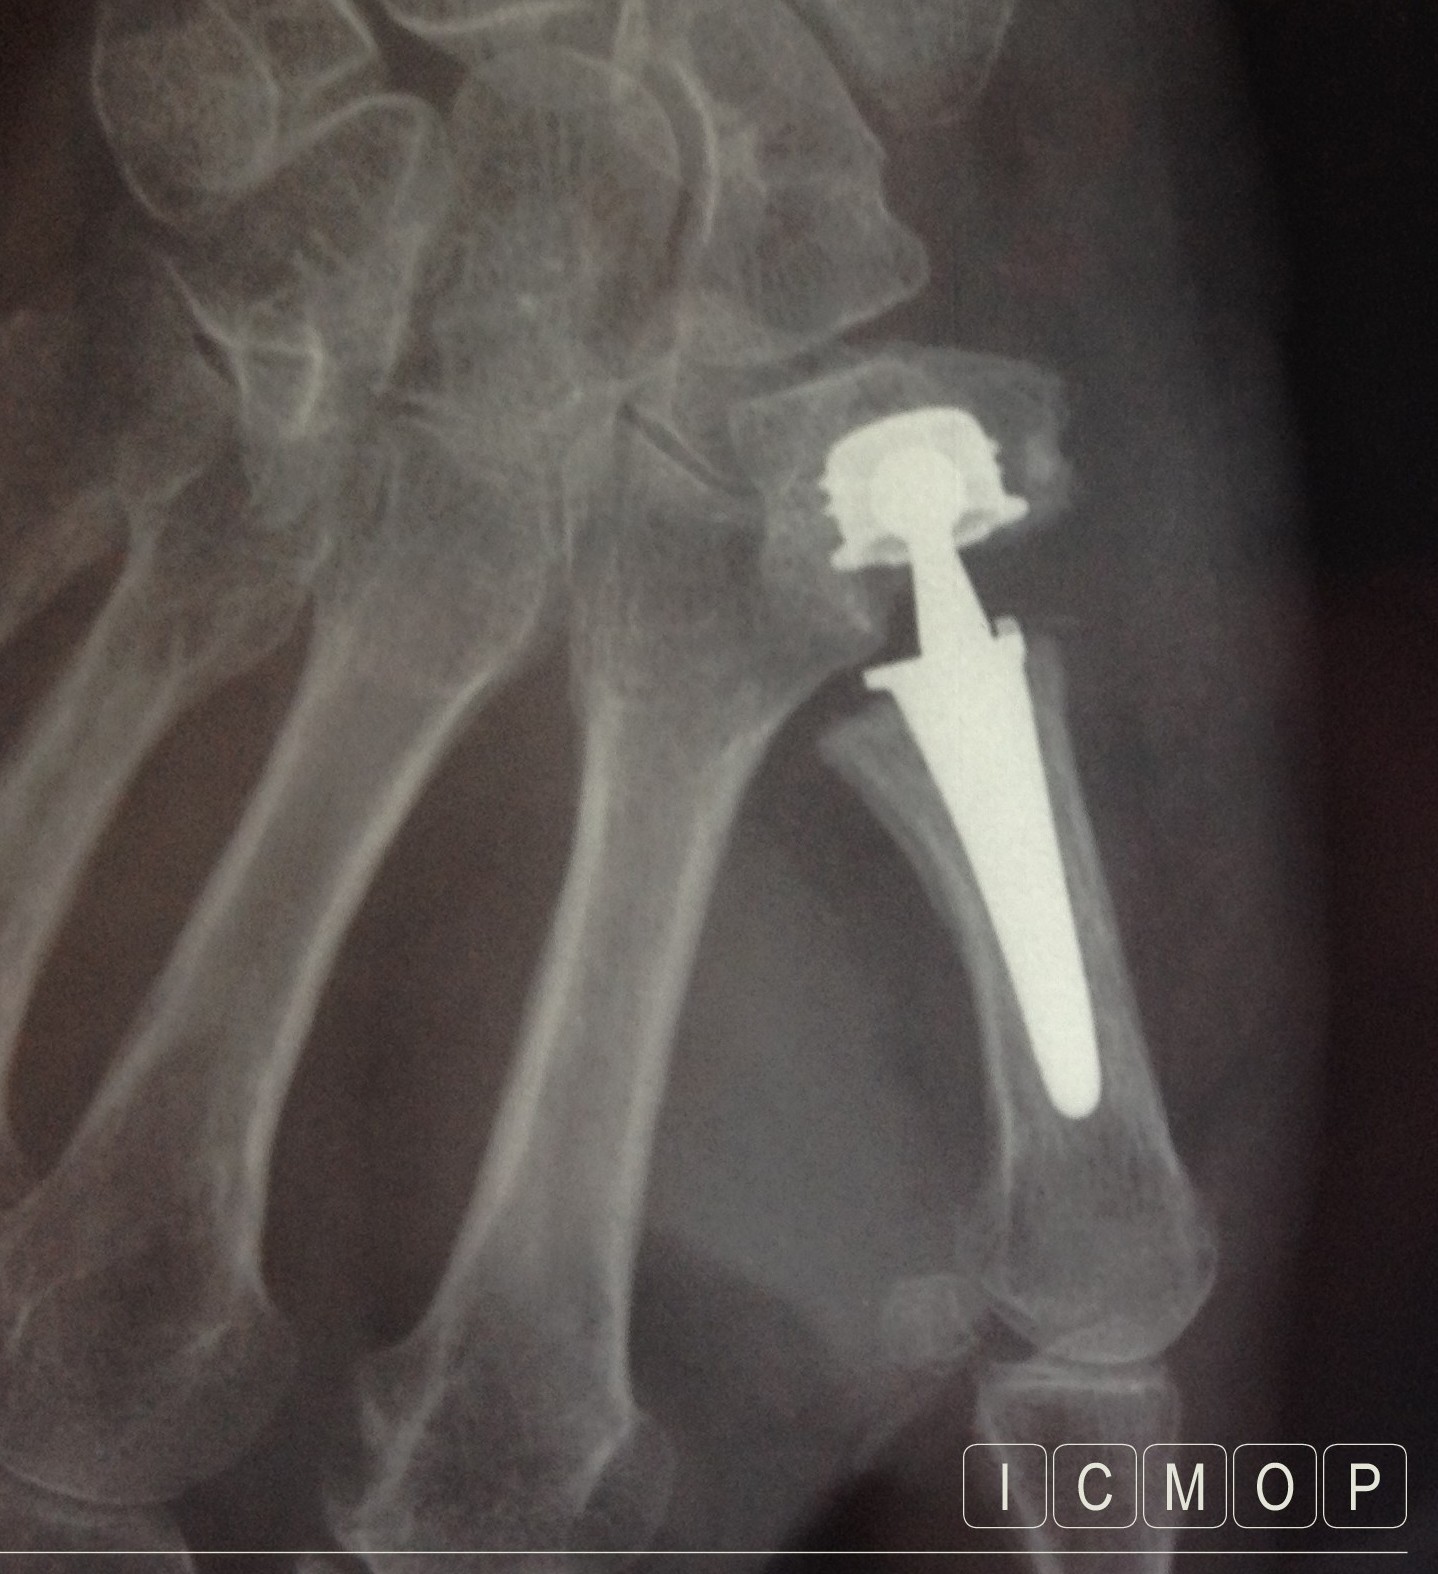

La prothèse trapézo-métacarpienne remplace les surfaces articulaires usées.

Les radiographies

elles sont nécessaires et suffisantes. Elles permettent d’évaluer la gravité de l’arthrose, l’épaisseur du trapèze, et la présence ou non d’une subluxation de la base du premier métacarpien.

• La prothèse permet une récupération beaucoup plus rapide mais se dégradera avec le temps. Il peut être nécessaire de refaire une chirurgie 10 ou 15 ans plus tard.